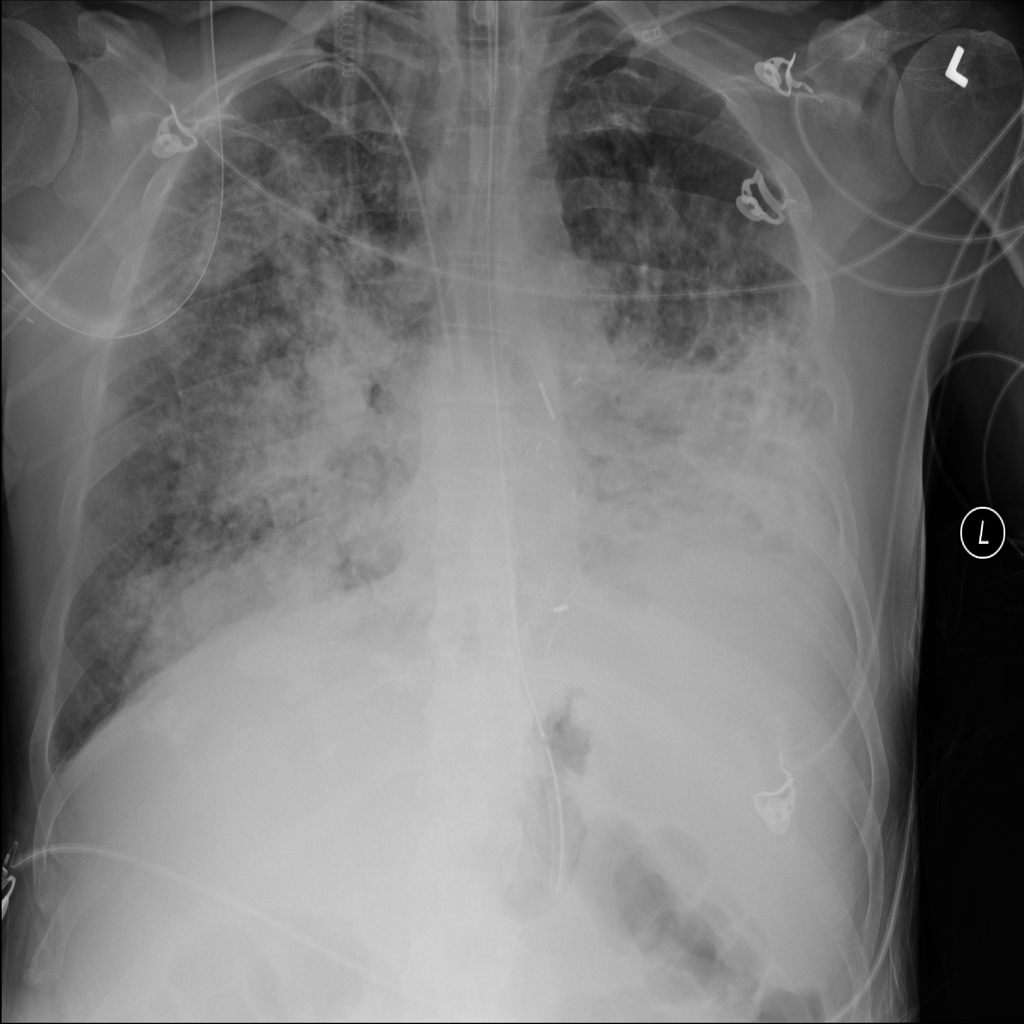

Showing up to 90 reference images for Nodule.

PAT-50E5 · IMG-000Nodule

PAT-50E5 · IMG-000

PA